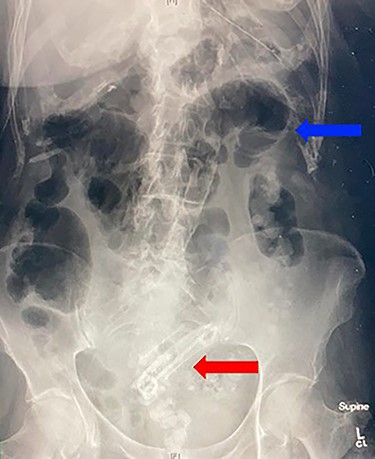

Abdominal X-ray demonstrating projection of biliary stents in the pelvis (red arrow) and multiple air fluid levels suggestive of a small bowel obstruction (blue arrow).

A 90-year-old female presented to the hospital for small bowel obstruction requiring surgery. Six months prior, she underwent an endoscopic retrograde cholangiopancreatography (ERCP) with sphincterotomy and insertion of side-by-side straight plastic stents followed by a laparoscopic cholecystectomy for cholangitis secondary to choledocholithiasis. The stents were to be removed 6 weeks post cholecystectomy; however, the procedure was delayed for 5 months due to significant deconditioning requiring prolonged physical rehabilitation. During the repeat ERCP, there were concerns for a biliary mucosal tear resulting in prophylactic insertion of two covered metal biliary stents with two plastic biliary stents in situ. She had an unremarkable hospital admission and was sent home the following day. Two weeks after the repeat ERCP, she presented to the emergency department with colicky abdominal pain, distention and bilious vomiting. Abdominal examination demonstrated a markedly distended abdomen with periumbilical tenderness on palpation. An abdominal X-ray revealed projection of the biliary stents in the pelvis (Fig. 1), with an abdominal computed tomography scan confirming the migration of stents to the small bowel resulting in a small bowel obstruction (Fig. 2A–C). An emergency mini-laparotomy was performed revealing seropurulent ascites and palpable biliary stents obstructing the proximal ileum causing upstream dilatation. A small enterotomy was performed, all four stents were retrieved (Fig. 3A–C) and the enterotomy was closed with interrupted full-thickness repair using 4.0 polydioxanone sutures. The patient had a slow progression due to prolonged ileus and was discharged from the hospital after 2 weeks.